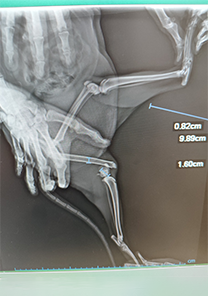

Feyza Hanım'ın Kedisi

Feyza Hanım'ın kedisi, üçüncü kattan düşmeye bağlı olarak femur distalinde kırık yaşamıştır. Femoral cross pin ile fiksasyonu sağlanmış ve Operasyon günü itibarıyla MN - HUND&KATT kullanılmıştır. Operasyonun ardından yürümeye başlayan kedinin pinleri 25 gün sonra çıkarılmış ve tamamen iyileşmiştir.